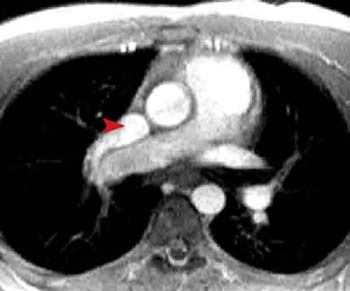

This congenital abnormality results in total (TAPVR) or partial (PAPVR) anomalous connection of the 4 pulmonary veins draining into the right heart circulation instead of the left atrium. The pulmonary veins can either enter the right atrium, SVC, or IVC below the diaphragm. Subdiaphragmatic APVR often causes vascular obstruction that leads to pulmonary edema in the lung drained by the anomalous pulmonary vein. This complex anatomy can be visualized effectively with cardiac MRI using cine imaging and MRA.

This gradient echo image in the axial plane shows the right superior pulmonary vein emptying into the SVC (arrowhead) rather than the left atrium. Therefore, oxygenated blood is entering the right side of the heart instead of the left. Other slices should be examined to study the course of the other pulmonary veins to determine if this is total or partial APVR.